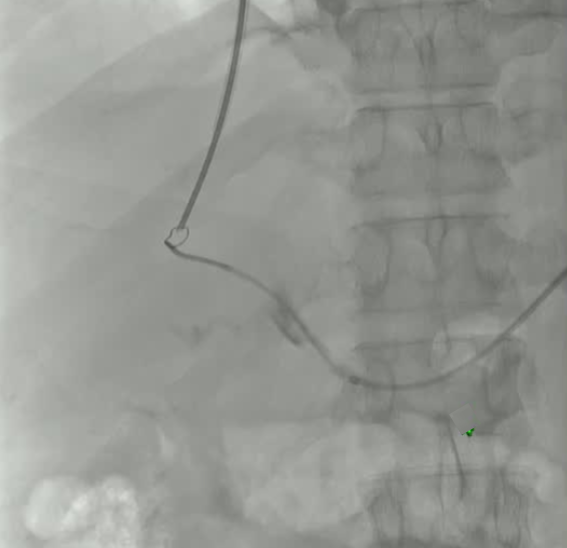

该程序包含以下步骤: 经脾脏入路:在超声引导下,刺穿脾静脉内的一个实质内分支。 在通过脾静脉造影确认了静脉通路后,导管和导丝被推进,以穿过脾静脉并抵达血栓化的门静脉。在门静脉/右门静脉分支处放置圈套器,为TIPS穿刺精准定位。TIPS穿刺圈套器,并穿过圈套器完成TIPS

步骤: 鉴于慢性血栓形成的复杂性: 一种经脾脏途径的门静脉再通术(PVR)。 随后是经颈静脉肝内门体分流术 。